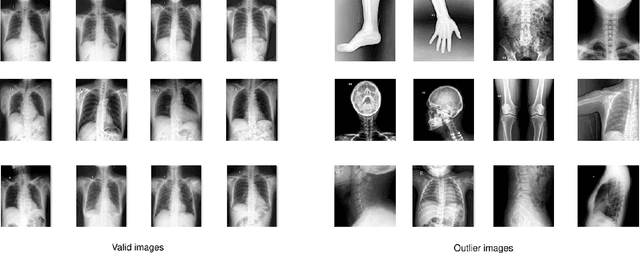

Abstract:Most of the existing chest X-ray datasets include labels from a list of findings without specifying their locations on the radiographs. This limits the development of machine learning algorithms for the detection and localization of chest abnormalities. In this work, we describe a dataset of more than 100,000 chest X-ray scans that were retrospectively collected from two major hospitals in Vietnam. Out of this raw data, we release 18,000 images that were manually annotated by a total of 17 experienced radiologists with 22 local labels of rectangles surrounding abnormalities and 6 global labels of suspected diseases. The released dataset is divided into a training set of 15,000 and a test set of 3,000. Each scan in the training set was independently labeled by 3 radiologists, while each scan in the test set was labeled by the consensus of 5 radiologists. We designed and built a labeling platform for DICOM images to facilitate these annotation procedures. All images are made publicly available in DICOM format in company with the labels of the training set. The labels of the test set are hidden at the time of writing this paper as they will be used for benchmarking machine learning algorithms on an open platform.